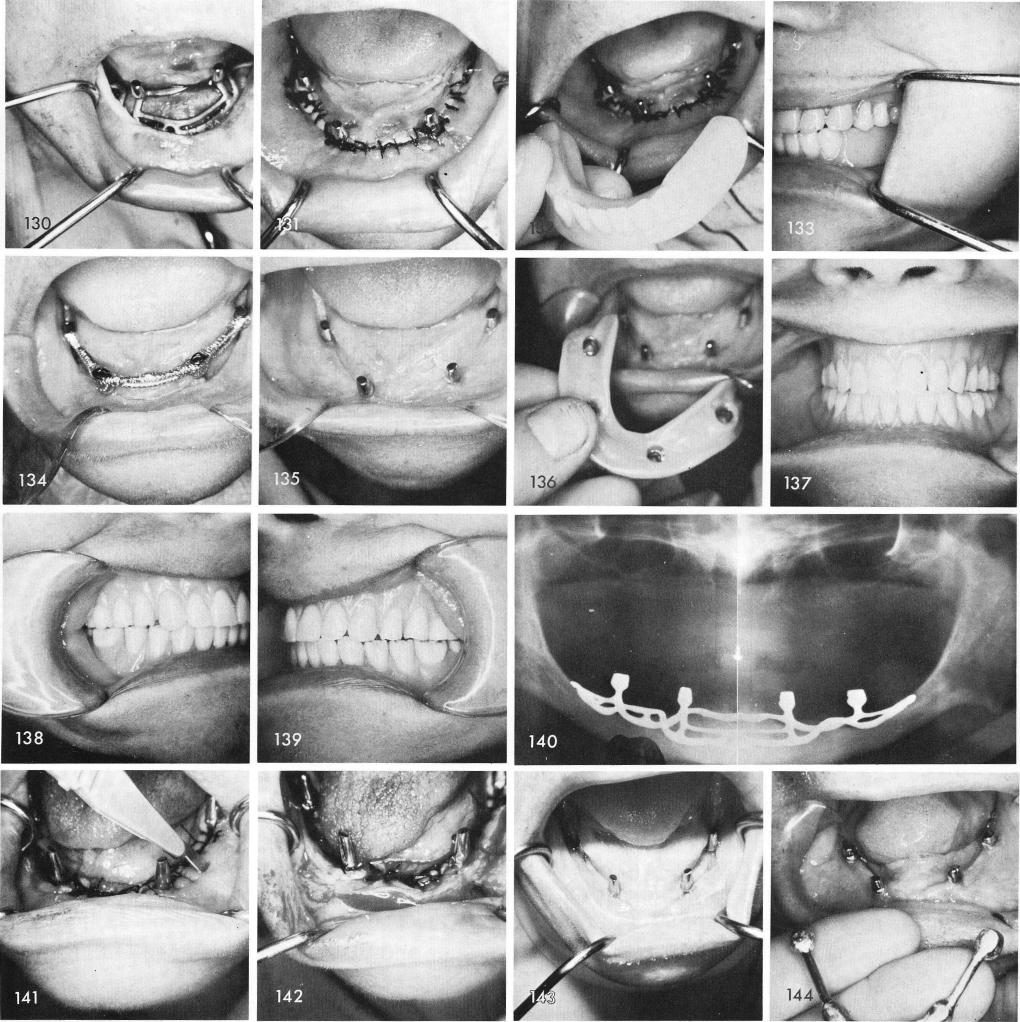

is fitted, fig. 134. The healed tissues, fig. 135, and the completed prosthesis, figs. 136, 137, 138, 139, and post-operative x-ray, fig. 140.

When it is difficult to suture the tissues together without having to pull too hard accessory incisions lateral and buccal to the implant framework directly through the tissues to the periosteum but not through it gives excellent results, figs. 141, 142, 143. Figs. 144, 145, 146, 147, 148 show another early case with short posts that needed further support.

1 Accessory incisions placed lateral and buccal to mandibular implant